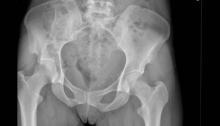

Trauma pelvico : Guías y clasificación WSES 2017.

Este artículo presenta la clasificación de traumatismo pélvico de la Sociedad Mundial de Cirugía de Emergencia (WSES) y el manejo del mismo.